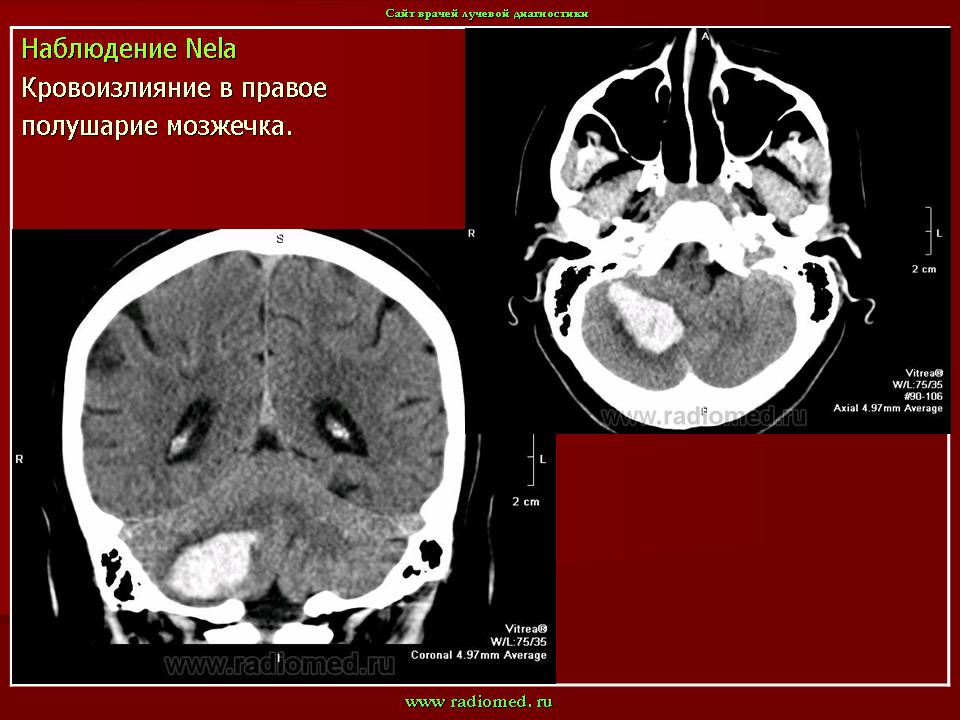

Мр картина венозной ангиомы левой гемисферы мозжечка - 96 фото